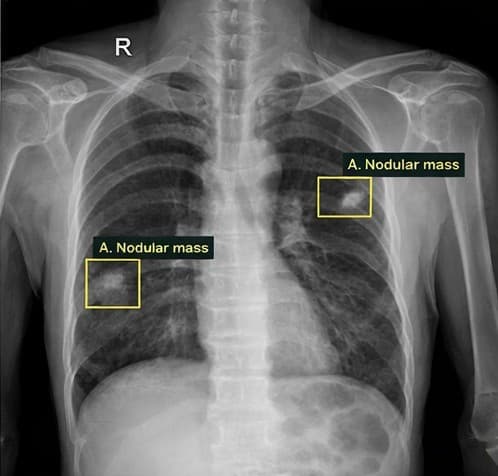

Lung tumor